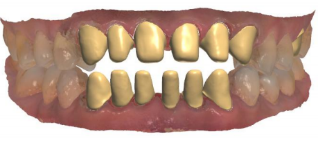

修复前的牙齿